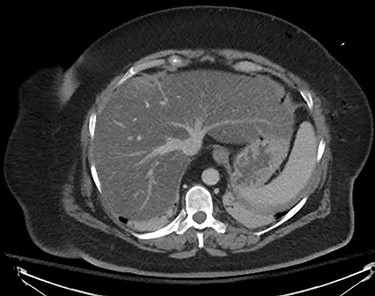

The planned cholecystectomy was not re-attempted, and the patient remained intubated. She underwent emergent infused CT chest and abdomen to rule out other injuries (Fig. 1). It showed severe fatty infiltration of the liver, with tracking of gas into the liver parenchyma. No other abnormalities were noted. It was evident that the needle had entered the liver, leading to a gas embolus. Uninfused CT brain and CT angiography later that day were unremarkable with no evidence of infarction and no abnormalities noted within cranial circulation.

CT thorax and abdomen, infused, immediately post-operative noting severe fatty infiltration within the liver and Veress needle track.